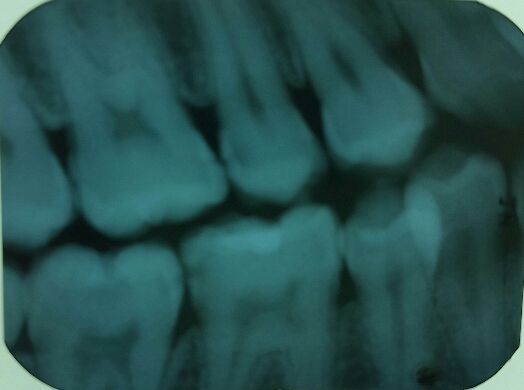

ทำเล่นๆ แต่อยากให้ตอบจริงสำหรับนทพ.ไว้ทบทวนการอ่าน film bitewing และการตรวจฟันผุเพื่อพิจารณาเลือกการรักษาที่เหมาะสมคุณพร้อมที่จะให้การรักษาคนไข้แค่ไหน

1 ในฟิล์มเห็นฟันผุด้าน proximal กี่ซี่ ซี่ไหนบ้าง

2 ซี่ 36D ผุถึงระดับไหน จำเป็นต้องอุดหรือไม่

3 ถ้าเห็นซี่ 37 แบบนี้คนไข้ไม่มีอาการอะไร ทำงัยต่อดี

4 ซี่ 37O ดูลึกจัง เชื่อมั๊ย ดูข้างนอกไม่เห็นเลยนะ enamel ปกติ จะต้องอุดแล้วละ ทำงัยดี

5 จากฟิล์ม เห็น 16M หน้าตายังงี้ แล้วทำงัยต่อ